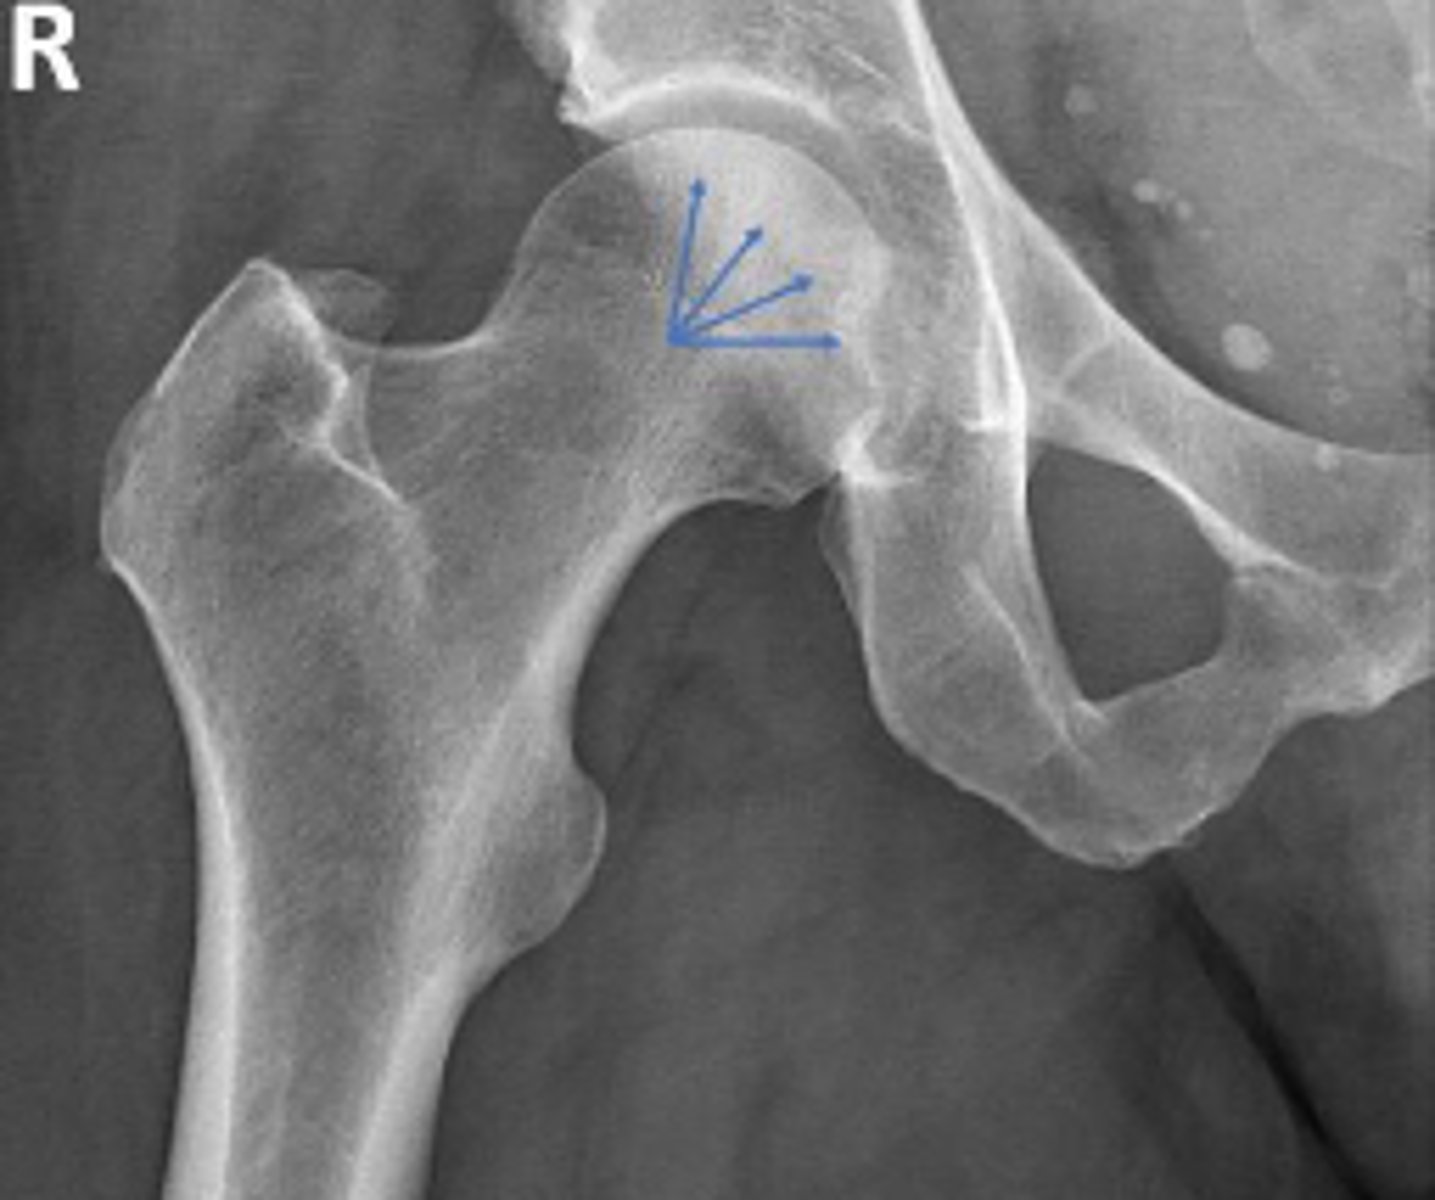

Center edge angle

What is the name of the assessment?

20-40 degrees

What is the normal range for this assessment?

A vertical line is drawn upwards from the center

of the head of the femur.

The second line is drawn from the center of the femur head to the outer superior-lateral aspect of the acetabulum

What are the osseous landmarks for this assessment

No (normal measurement is 20-40 degrees)

Is the measurement within normal limits?

Acetabular dysplasia

Developmental dysplasia of the hip

Name 1 condition that may result in a measurement <20 degrees?

AP pelvis and AP hip views

Name 2 radiographic views for this assessment?